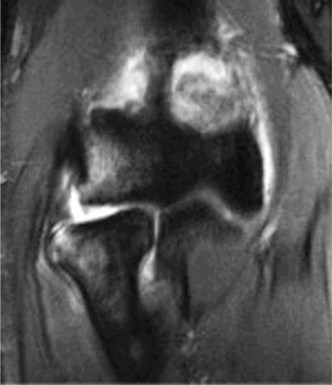

You send the patient for an MRI, which is shown in Figure 2–66.

Figure 2–66

Based on the clinical examination and imaging, what is the most likely etiology of the patient’s symptoms?

The correct answer is (C). The patient’s clinical examination findings of isolated

weakness in external rotation and atrophy of the infraspinatus muscle point to suprascapular nerve entrapment at a location past the exit point for the branch to the supraspinatus muscle. Also, MRI reveals a posterior labral tear with a paralabral cyst that is compressing the suprascapular nerve at the spinoglenoid notch. Choice A, while fitting with the patient’s clinical examination, does not fit with the MRI showing paralabral cyst. Choices B and D are incorrect because entrapment of the suprascapular nerve at the suprascapular notch by scapular body fracture or by the transverse scapular ligament (more common) would lead to weakness/atrophy in both supraspinatus and infraspinatus muscles as the suprascapular notch is proximal to the nerve branch point to the supraspinatus muscle.